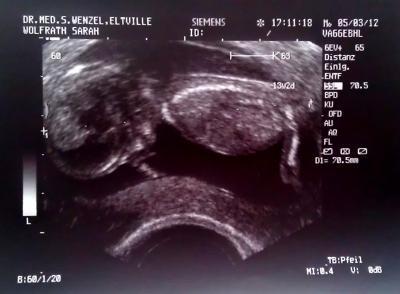

Hallo Mädels, war ja vorhin außerplanmäßig beim Arzt, es ist alles bestens :-) Das Baby ist putzmunter und hat sich wild gedreht und gestrampelt. Ich bin soooo überglücklich. Die Nackenfaltemessung hat 1,2 cm ergeben, also alles im totalen Normbereich. Baby ist mittlerweile 7 cm groß und es wird sehr wahrscheinlich ein Mädchen :-) Das Baby hat sich kurz auf den Bauch gedreht so das man die angeblichen Scharmlippen sehen konnte. Bin ja mal gespannt ob es dabei bleibt :-) Hab auch ein totalllll tolles Bildchen bekommen, schaut mallllll :-) Danke fürs Däumchen drücken.

Bild zu Zurück vom Arzt :-) super glücklich und mit tollem Bildchen.... - Forum für September - Mamis